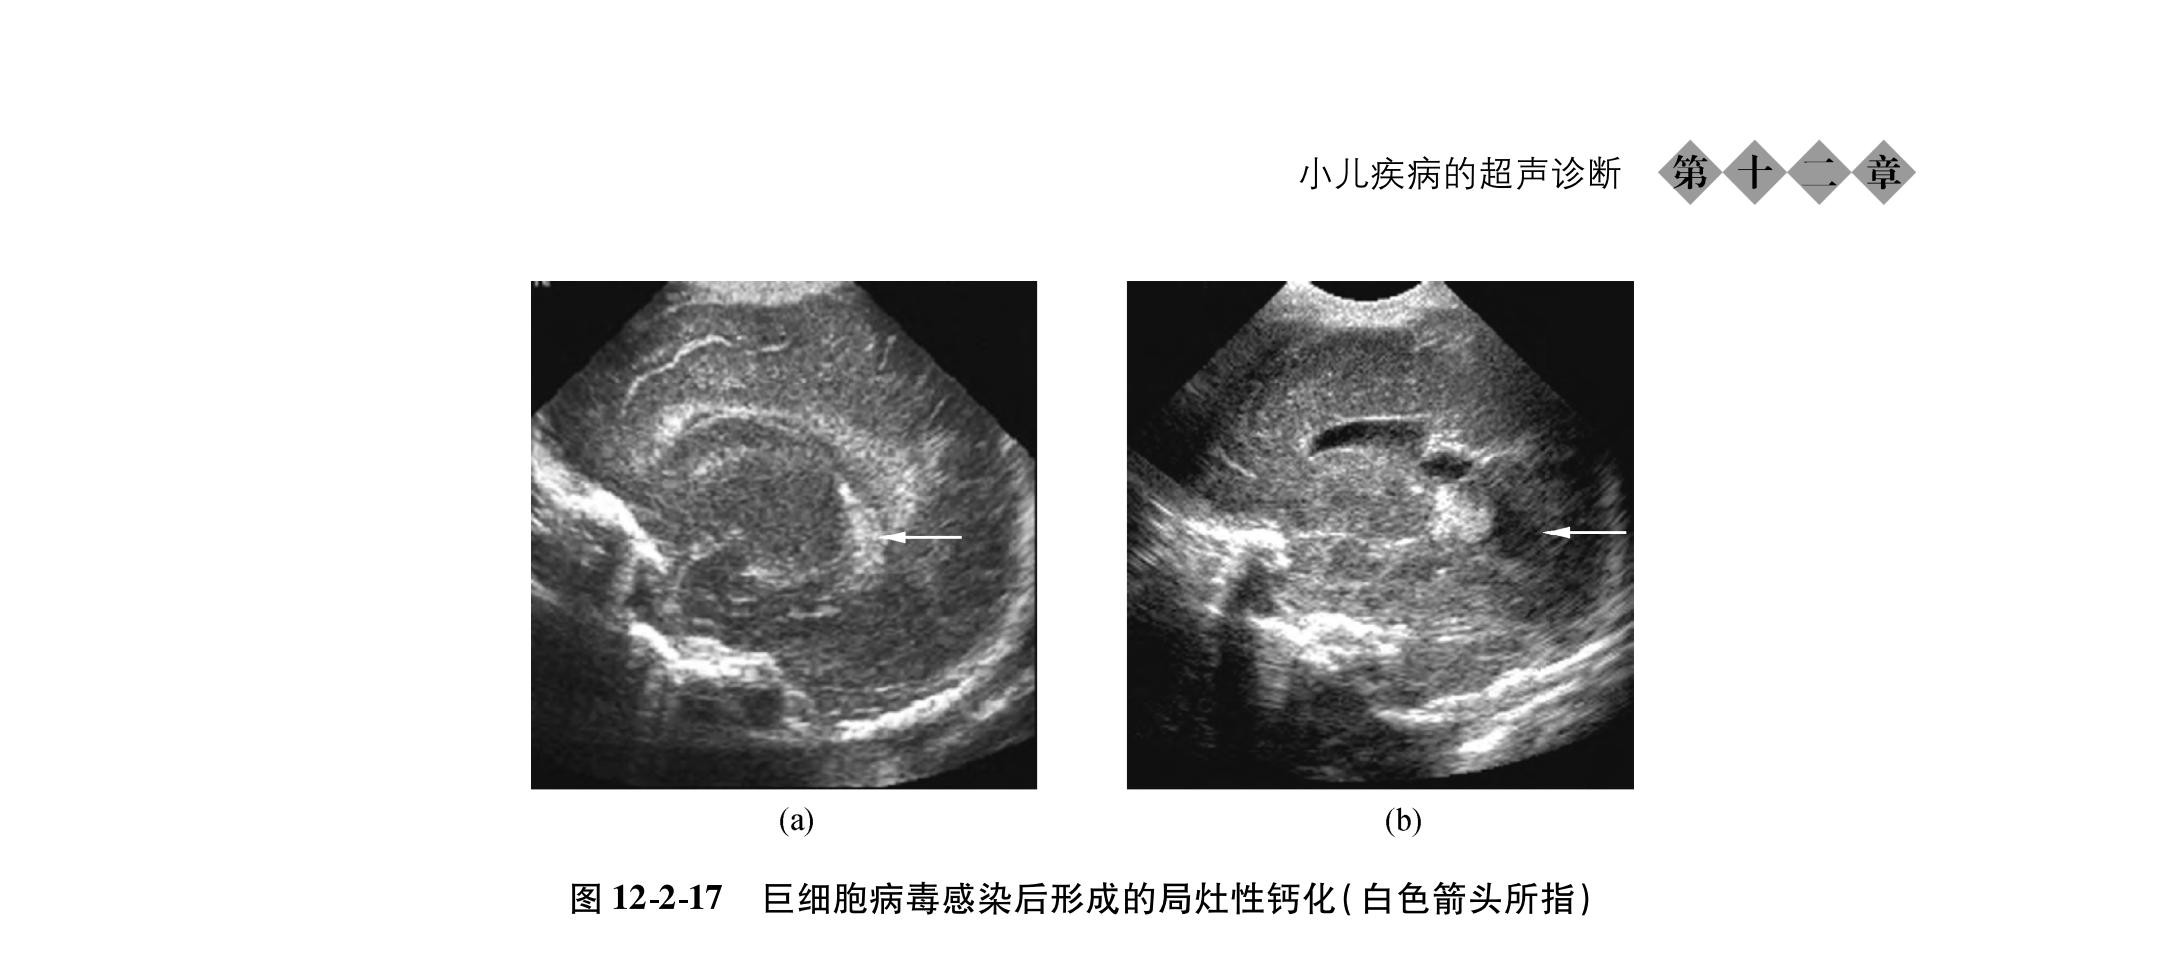

新生儿颅脑的超声诊断